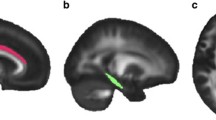

The DTI data were motion and eddy current corrected using the FLIRT and FUGUE algorithms from Free-Surfer Library (FSL) (http://www.fmrib.ox.ac.uk/fsl), and an additional geometric distortion correction was performed. The DTI images were then co-registered to the T1 image and up-sampled to the T1 resolution. Fractional anisotropy (FA) maps were calculated using the teem algorithms (teem.sourceforge.net). An unbiased project specific FA atlas in MNI152 space was generated from the all images using the fast, high degree diffeomorphic image registration algorithm (DARTEL) implemented in SPM8 (http://www.fil.ion.ucl.ac.uk/spm). The FA maps of all subjects were warped onto the FA atlas using DARTEL. Labels from the ICBM DTI81 atlas (created by hand segmentation of a standard-space average of diffusion MRI tensor maps from 81 healthy subjects) were used to extract mean FA values from the six white matter tracts of interest (Fig. 1), voxels with FA < 0.2 were masked out to reduce partial volume effects from neighboring gray matter regions. The mean FA values from the left and right tract were combined after excluding a hemispheric effect.

Veterans with PTSD were compared to combat-exposed controls on six, long associational white matter tracts using ANCOVA (Table 2 and Fig. 2), covarying for age and comorbidities (LOC < 10 min and cardiometabolic diagnoses). The PTSD group exhibited significantly higher FA values relative to controls in the SFOF tract (p = .034) and borderline higher FA in the ACR (p = .054) and CGC (p = .077), while controlling for age and comorbidities. No differences were present in the UF, IFOF or SLF. Age was not a significant predictor, potentially due to relative youth of the sample (mean age: 33 years; range: 22–55). Medical comorbidities, including LOC and cardiometabolic diagnoses, were a significant predictor of higher SFOF FA, independent of PTSD.

This is one of the largest studies to date of white matter abnormalities associated with combat-related posttraumatic stress disorder (PTSD). This study excluded participants meeting criteria for moderate to severe traumatic brain injury (TBI) or for alcohol dependence in the prior 8 months. Relative to combat-exposed controls, veterans with combat-related PTSD exhibited higher fractional anisotropy (FA) in the superior fronto-occipital fasciculus (SFOF) and borderline higher FA in the anterior corona radiata (ACR) and cingulum (CGC), controlling for age and neurovascular comorbidities. When we additionally controlled for lifetime history of alcohol use disorders (AUD), which was elevated in veterans with PTSD, it reduced the association of PTSD with higher FA in the ACR and cingulum, but did not explain the association with higher FA in the SFOF. These tracts provide structural connections for a corticolimbic network, previously identified by a meta-analysis of abnormal functional connectivity in PTSD (Etkin and Wager 2007). Higher FA is typically thought to be associated with greater axon diameter, density, or myelination, indicating relative enhancements of white matter integrity (Beaulieu 2002). However, important caveats exist (Jones et al. 2013), and higher FA is also found in the context of psychiatric and neurocognitive pathology (Hoeft et al. 2007; Abe et al. 2006; Davenport et al. 2010). In addition, exploratory tract-symptom relationships were present among veterans with PTSD. Due the cross-sectional nature of these findings, it is unclear whether white matter alterations may play a precipitating role in PTSD or reflect a compensatory response to neuroinflammatory stimuli such as psychological trauma and heavy alcohol use.